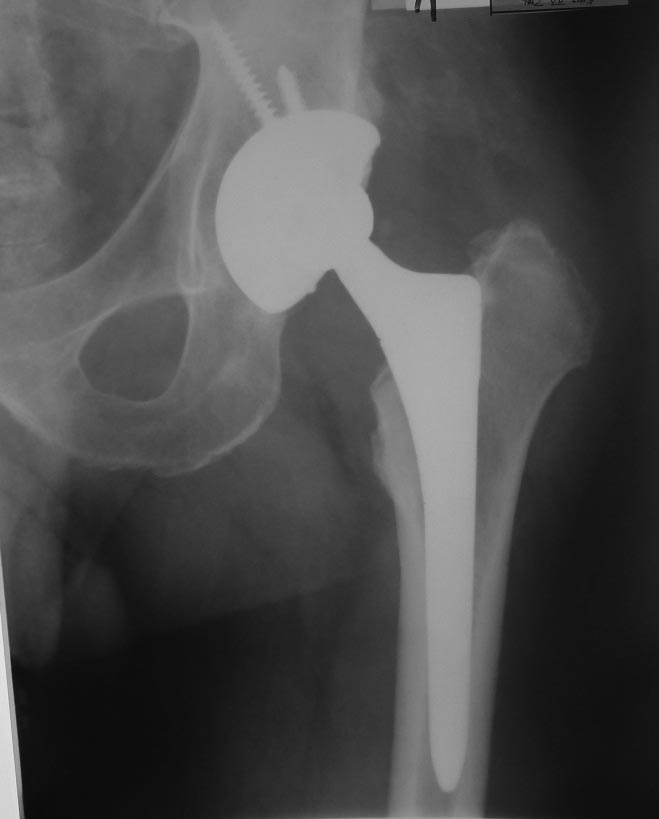

Эндопротезирование пациенту 49 лет выполнил в 2007 г. по поводу

коксартроза. В начале мая 2013 г. в состоянии запоя он упал со скамейки,

Последние (июньские) рентгенограммы без особенностей (прилагаются).